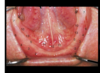

ID 1

labial frenum